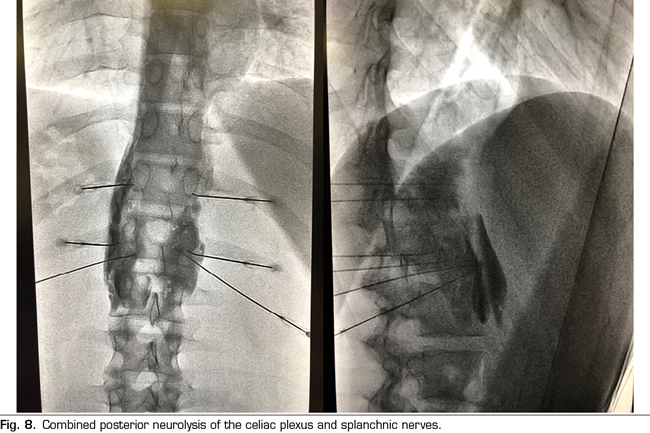

Following the conclusions of the previously described publications, an interventional treatment algorithm for patients with visceral pain associated with pancreatic cancer can be established (Figure 7). The standard procedure would be the posterior approach of the celiac plexus (classical approach), since today it continues being the one with the greatest scientific evidence, preferably transcrural and guided by fluoroscopy, due to its simplicity and speed. Ultrasound endoscopy would be indicated for neurolysis taking advantage of its diagnostic or therapeutic indication, for situations of inability to prone position, and as an alternative in case the posterior approach fails. Percutaneous ultrasound neurolysis would be reserved for selected cases, depending on the experience of the operator, since it is the technique that has fewer publications to date. We hope that in the future, studies allowing ultrasound-guided techniques, whether percutaneous or endoscopic ultrasound, will be published as the “reference method”, since they allow the visualization of surrounding structures with real-time injection control. An alternative to the blockage of the celiac plexus is the conventional radiofrequency of the splanchnic nerves, indicated when there is tumor infiltration of the celiac trunk, important anatomical alterations or if the celiac plexus neurolysis fails. It is also possible to consider a combined neurolysis - neurolytic blockade of the celiac plexus associated with neurolytic block or radiofrequency of the splanchnic nerves -, as reflected in the study of Marra et al. (60), and as we have been performing in our usual clinical practice at HM hospitals, with the aim of increasing the success rate and duration of analgesia without increasing the incidence of complications. However, no enough comparative studies supporting this hypothesis are available so far (Figure 8).